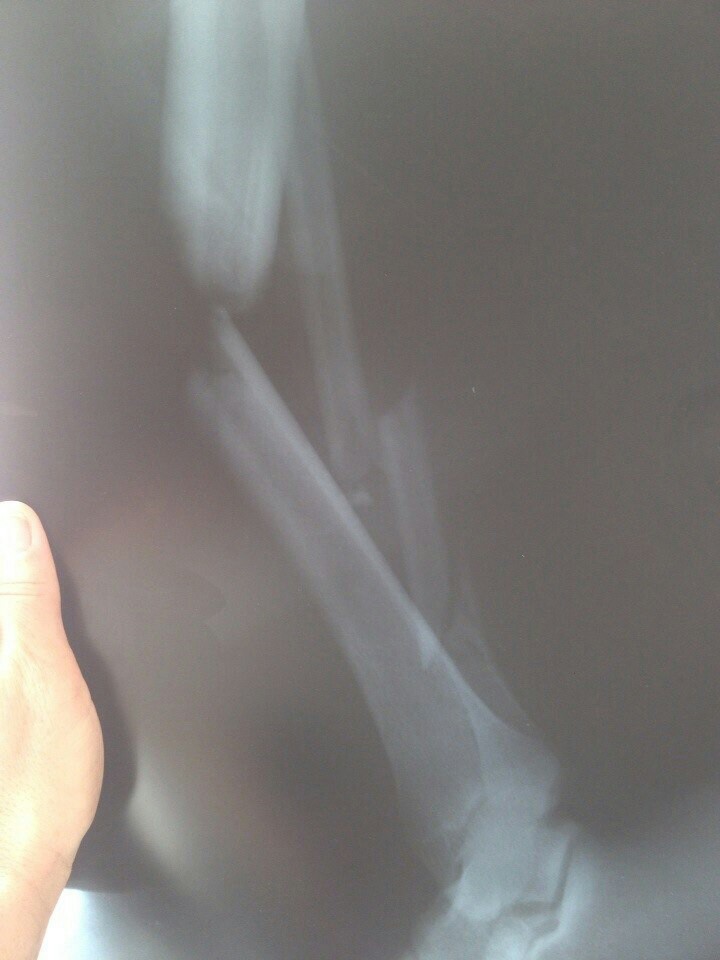

Всем привет! 3 августа 2014, около 5-6 часов утра, я попал в ДТП на мотоцикле (врезался в бетонный отбойник). Произошло это на Ленинградском шоссе, не далеко от солнечногорска, если в сторону Москвы ехать, в районе села Пешки. При ударе в отбойник я потерял сознание, очнулся только через 30-40 минут, с открытым переломом правой ноги и потеряв при этом почти 2,5л крови (это как потом врачи сказали). Я сразу начал звонить в скорую и попутно махать рукой что бы кто нибудь остановился. Скорой я пытался объяснить где нахожусь, но от шока и боли я не мог точно понять где я нахожусь. Но тут остановился какой то мужчина и поняв что я разговариваю по телефону со скорой, отобрал его и сказал им где я нахожусь. Он сразу же перетянул мне ногу верёвкой и накрыл какой то фольгой. Также он не давал мне потерять сознание до приезда скорой и поил меня. Потом приехала скорая минут через 20 вколола обезболивающее и увезли в больницу.

Я к тому это, что в больнице мне сказали, если бы не мужик который перетянул мне ногу, они бы не успели меня спасти из-за большой потери крови.